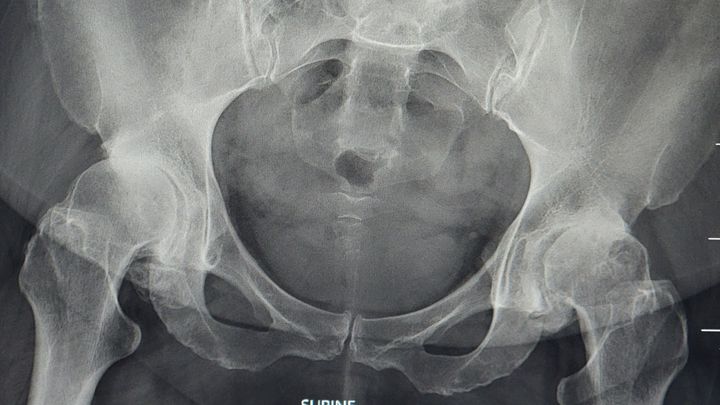

Our sassy, sweet Shalyna needs our help to get through not working, while she's waiting for her surgeries and recovery. She's been working the past couple years, past the point that she should have. Anyone who knows her knows that she is tough and almost unstopabble. Unfortunately, she is no longer physically able to work now. Fortunately, covid waits on surgery are over. The Dr's are ready to get her started on her path. Her hips don't lie, they're not even going the right direction,lol. When I saw her Xray I couldn't believe she was working like that! But, providing for her family was so important to her that she set all that pain aside. And even made jokes and laughed her way through it. She's a huge inspiration to me and probably the person reading this too. She's been so generous; it's time for us to give back to her for once. Thoughts and prayers are great, but I'm asking for cash money, lol. But seriously, let's all help out our girl! Much love Shalyna!